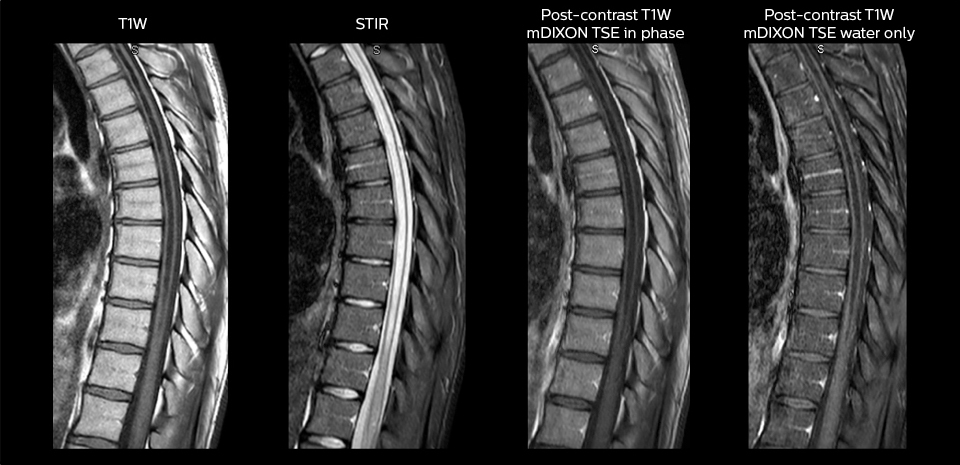

„Mit mDIXON TSE-Sequenzen ist es dank der T2-gewichteten Bilder auf Wasserbasis aus derselben Erfassung möglich, gleichzeitig morphologische Veränderungen aus den T2-gewichteten In-Phase-Bildern zu charakterisieren und ödematöse Veränderungen darzustellen. Auf diese Weise können anatomische und morphologische Befunde wie eine partielle oder komplette Bandruptur, ein knöcherner Ausriss oder ein Hämatom abgeklärt werden.“ „In Bezug auf die Beurteilung von Weichteilgewebe bietet mDIXON ähnliche Vorteile. Bei einer T2-gewichteten mDIXON TSE-Erfassung helfen die multiplen Kontraste zum Beispiel bei der Abklärung von pathologischen Befunden in Faserbündeln der peripheren Nerven, die auf anatomischen oder entzündlichen Veränderungen beruhen können.“ „Bei peripheren Gelenken erhalten wir mit mDIXON TSE eine gute Qualität in diffizilen Bereichen. Bilder mit Fettsuppression erscheinen vollständig homogen, auch bei einer großen Abdeckung mit 3,0 T – zum Beispiel beim Schulter- oder Beckengürtel – bzw. in den Gelenkflächen oder um Metallprothesen herum*, wo eine Fettsuppression mit STIR oder spektraler Suppression häufig unzureichend ist und zu Schwierigkeiten bei der Diagnose führt. Wenn ein diagnostisches Bild auf Anhieb richtig dargestellt wird, ist es nicht nötig, eine Sequenz zu wiederholen oder hinzuzufügen.“ „Mit mDIXON TSE-Sequenzen ist es dank der T2-gewichteten Bilder auf Wasserbasis aus derselben Erfassung möglich, gleichzeitig morphologische Veränderungen aus den T2-gewichteten In-Phase-Bildern zu charakterisieren und ödematöse Veränderungen darzustellen. Auf diese Weise können anatomische und morphologische Befunde wie eine partielle oder komplette Bandruptur, ein knöcherner Ausriss oder ein Hämatom abgeklärt werden.“ „In Bezug auf die Beurteilung von Weichteilgewebe bietet mDIXON ähnliche Vorteile. Bei einer T2-gewichteten mDIXON TSE-Erfassung helfen die multiplen Kontraste zum Beispiel bei der Abklärung von pathologischen Befunden in Faserbündeln der peripheren Nerven, die auf anatomischen oder entzündlichen Veränderungen beruhen können.“

„mDIXON TSE wird in unserer Notaufnahme ausgiebig für die Wirbelsäulenbildgebung eingesetzt“, führt Dr. Karis aus. „Besonders vorteilhaft ist, dass dieses Verfahren im Hinblick auf suszeptibilitätsbezogene Probleme sehr stabil ist, die häufig bei klassischen spektralen, fettgesättigten Bildern auftreten. Im Wesentlichen treten derartige Probleme beim mDIXON-Verfahren überhaupt nicht auf. Wir sind wirklich froh, in unserer Notaufnahme über die fettfreie Bildgebung des mDIXON-Verfahrens zu verfügen.“

„Für die routinemäßige, kontrastmittelfreie Untersuchung der Brust- und Halswirbelsäule führen wir zum Beispiel eine mDIXON T2-TSE-Sequenz durch, die uns zwei Ergebnisse liefert: die T2-gewichteten Bilder auf Fett- und Wasserbasis sowie die sagittalen T2-gewichteten Bilder auf reiner Wasserbasis. Anschließend erfolgt noch eine axiale Gradientenecho-Untersuchung.“